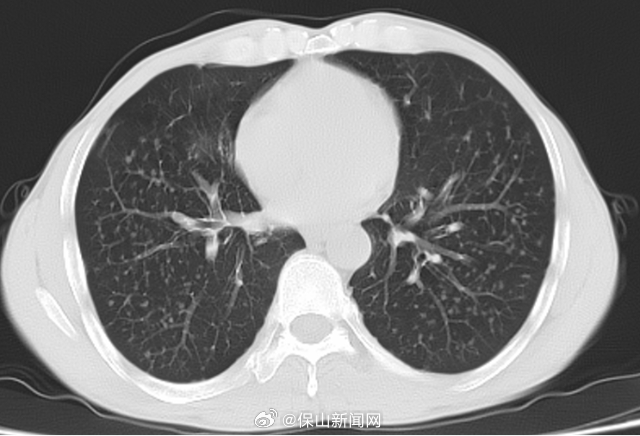

12年粉尘肺终获新生!保山医生从患者肺里洗出2000毫升“墨水”

48 岁建筑工人李先生因长期接触水泥粉尘,咳嗽气喘一年多,双肺 CT 呈弥漫性黑影。3月11日,保山市人民医院呼吸科团队为他实施全肺灌洗术,3 小时洗出近2000毫升 黑色浑浊液体,内含碳末、金属颗粒等 “工业废料”。术后李先生呼吸顺畅、体力恢复,直呼 “重获新生”!医生提醒:早发现、早干预可有效进行治疗,粉尘作业需严格做好防护,出现持续咳嗽、活动气短等症状应及时就医。#职业健康防护#